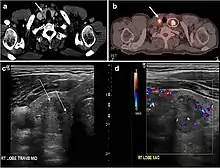

Fig. 9. A 58-year-old male patient with persistence PTC at thyroid bed with hypervascular nodal metastasis. a–c Transverse greyscale and colour Doppler neck ultrasound demonstrate hypoehoic soft tissue in the left thyroid bed (white arrow in a). There are a heterogeneous enlarged lymph nodes at level 2 and 3 with markedly increased vascularity (white arrow in b and c). d–f Enhanced axial CT images of the neck demonstrate a 2.7 × 1.4 cm hypodense soft tissue lesion anterior to the left carotid sheath (white arrow). There are left-sided enhancing abnormal and enlarged lymph nodes at cervical level 2 and 3 (black arrows).[1]